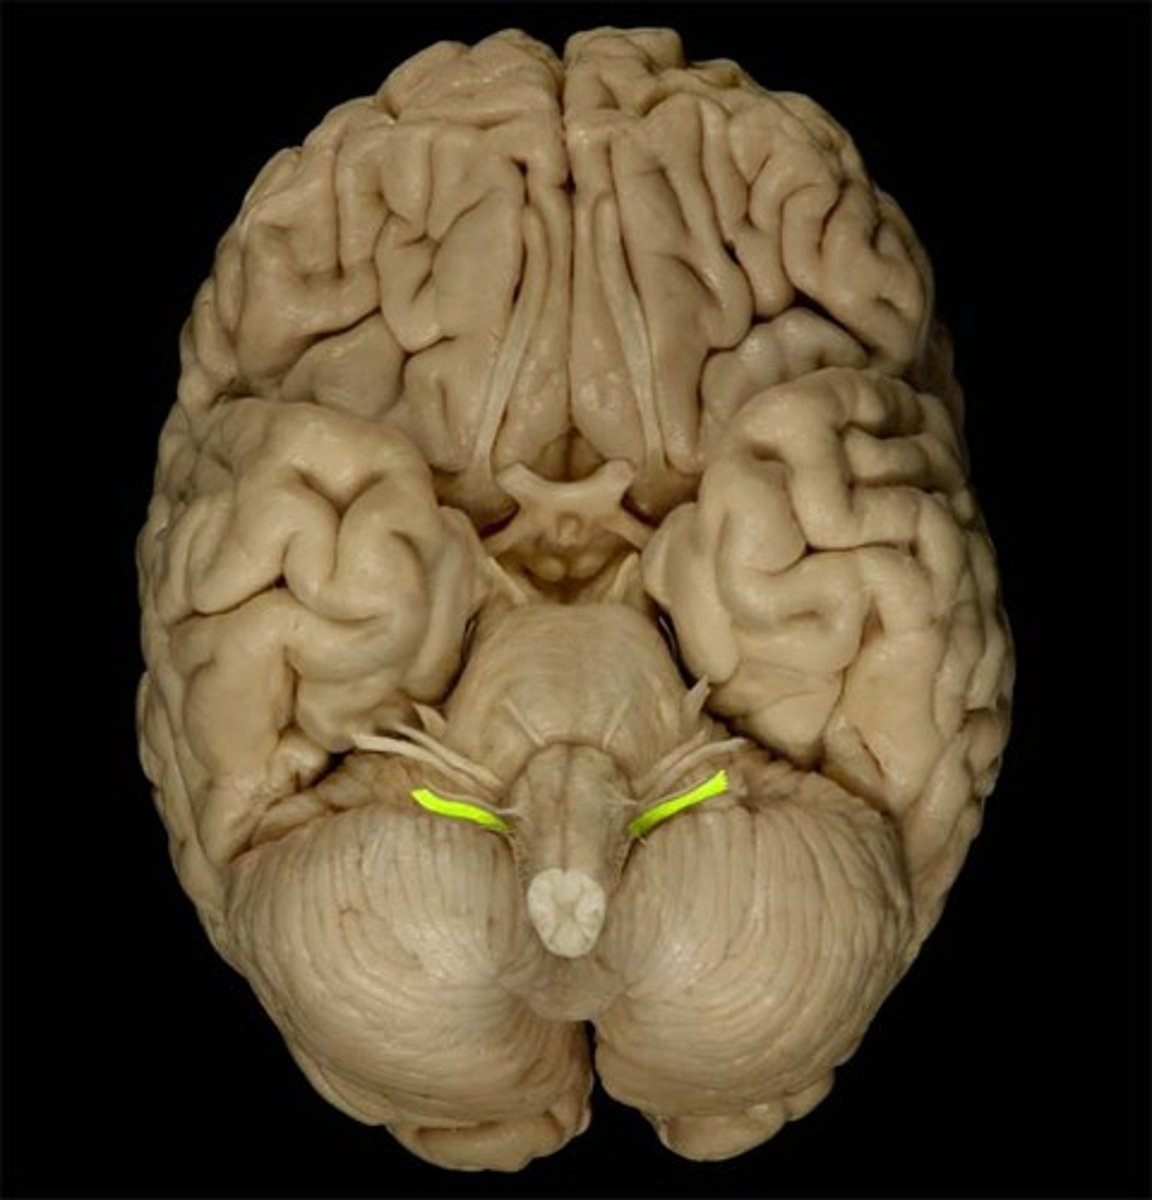

Caudate Nucleus

Globus Pallidus

Putamen